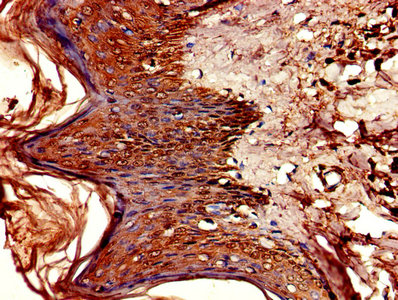

CSB-PA006046LA01HU

Immunohistochemistry of paraffin-embedded human skin tissue using CSB-PA006046LA01HU at dilution of 1:100